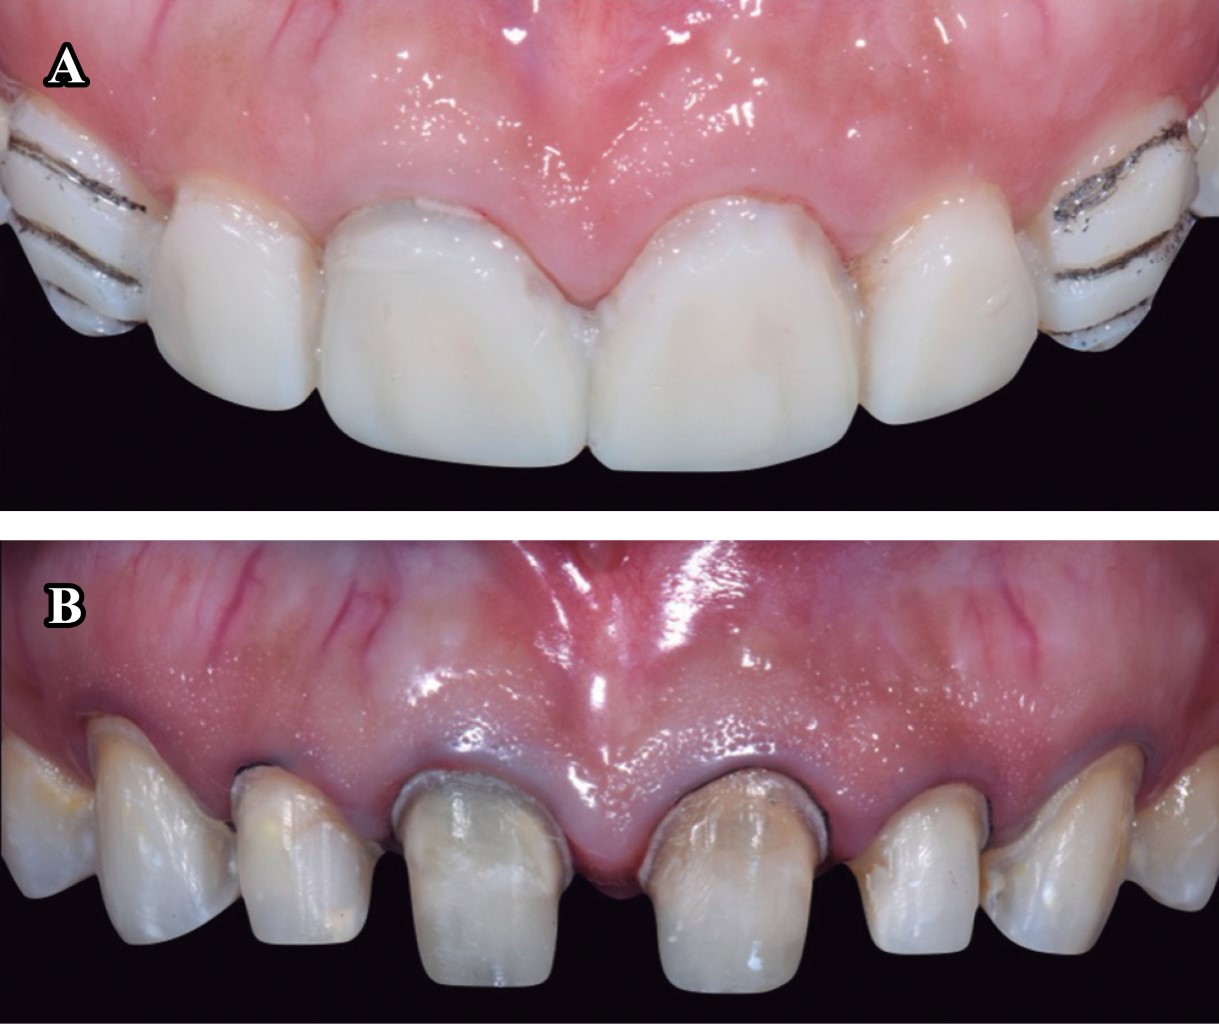

El plan de tratamiento requirió de un trabajo interdisciplinario en el que se indicó tratamiento de conductos y coronas de disilicato de litio (e.max, Ivoclar Vivadent) en los incisivos centrales y laterales superiores; carillas del mismo material en los caninos superiores izquierdo y derecho (Figura 1). Para iniciar el tratamiento se tomaron modelos de estudio, registro de mordida (Occlufast, Zhermack) y arco facial para montar los modelos en un articulador semiajustable (PCH-Panadent) (Figura 2). Posteriormente se realizó encerado diagnóstico para la confección de un Mock-up (Figura 3), en donde se evalúa la función de la nueva guía anterior establecida y deben ser realizadas pruebas de fonética y estética.

Una vez terminada la fase diagnóstica en donde se evalúan factores estéticos como las formas anatómicas, proporciones dentales, exposición de bordes incisales en reposo y funcionales devolviendo la guía anterior, se retiraron las coronas de los órganos dentarios (OD) 11 y 21, al igual que las lesiones cariosas de los OD 12 y 22 (Figura 4). Se realizó una interconsulta con el departamento de endodoncia y se procedió a realizar tratamiento de conductos a estos dientes. Una vez terminados los tratamientos de conductos se colocaron postes metálicos paralelos (Para-Post) en los OD 11 y 21 debido a que se necesitaba aumentar la altura del muñón protésico para retención de la restauración.10 Una vez sellados los tratamientos de conductos de las cuatro piezas se volvió a colocar el Mock-up para utilizarlo como guía de desgaste para las preparaciones dentales mínimamente invasivas (Figura 5).

Para el acondicionamiento del diente, se grabó el esmalte con ácido ortofosfórico 37% durante 20 segundos, seguido de un lavado con agua para posteriormente aplicar un adhesivo universal (Ivopen, Ivoclar). Se procedió a cementar las restauraciones con cemento Variolink Esthetic LC (Ivoclar Vivadent) fotocurándolo durante 3 segundos antes de retirar excedentes y para realizar un fotocurado final de 20 segundos por cada cara libre. Finalmente, se fotocuró sobre una capa de glicerina para eliminar la capa inhibida por oxígeno. Se puede observar un cambio estético (Figura 7) y funcional con el restablecimiento de la guía anterior (Figura 8) en comparación con la situación inicial, además se realizó un guarda oclusal con acrílico termocurado.